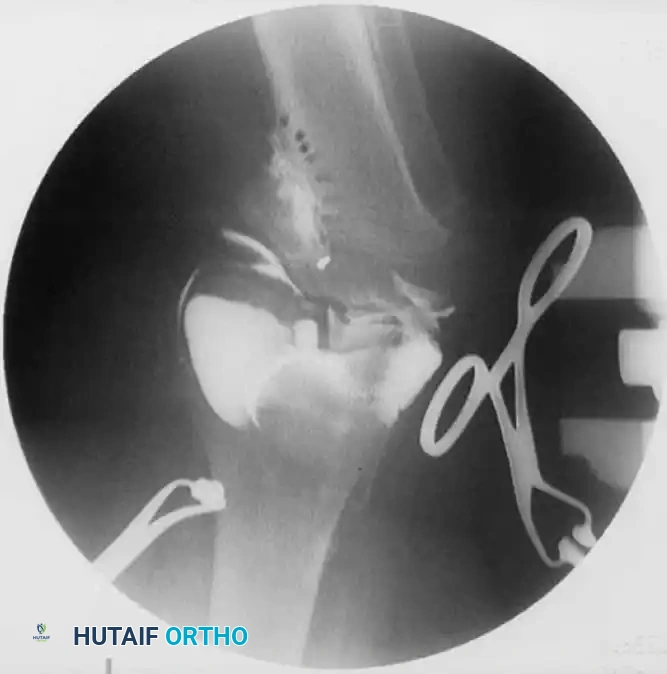

- Osteotomy Execution: Guide pins are placed under fluoroscopic guidance to define the osteotomy plane. The cut is made distal to the tibial tubercle to ensure the extensor mechanism remains attached to the proximal fragment.

- Deformity Correction: The distal fragment is translated laterally, angulated into valgus, and externally rotated to correct the multiplanar deformity.

- Fixation: Fixation depends on surgeon preference and patient age. Options include crossed Kirschner wires incorporated into a long-leg cast, rigid internal fixation (plates and screws), or external fixation (Ilizarov or Taylor Spatial Frame), which allows for gradual postoperative correction.

1. Intraepiphyseal Osteotomy: To elevate the depressed medial tibial plateau and reconstruct the horizontal joint line.

2. Metaphyseal Valgus Osteotomy: To correct the diaphyseal varus angulation.

Schoenecker et al. reported successful elevation of the medial tibial plateau in patients aged 10 to 13 years with average preoperative varus deformities of 25 degrees. The procedure involves an osteotomy through the epiphysis, elevating the medial plateau to match the lateral plateau, and supporting the elevation with structural bone graft.

Surgical Warning: Intraepiphyseal osteotomies carry a high risk of intra-articular fracture, avascular necrosis of the elevated fragment, and permanent physeal arrest. Meticulous fluoroscopic guidance and rigid fixation are absolute requirements.